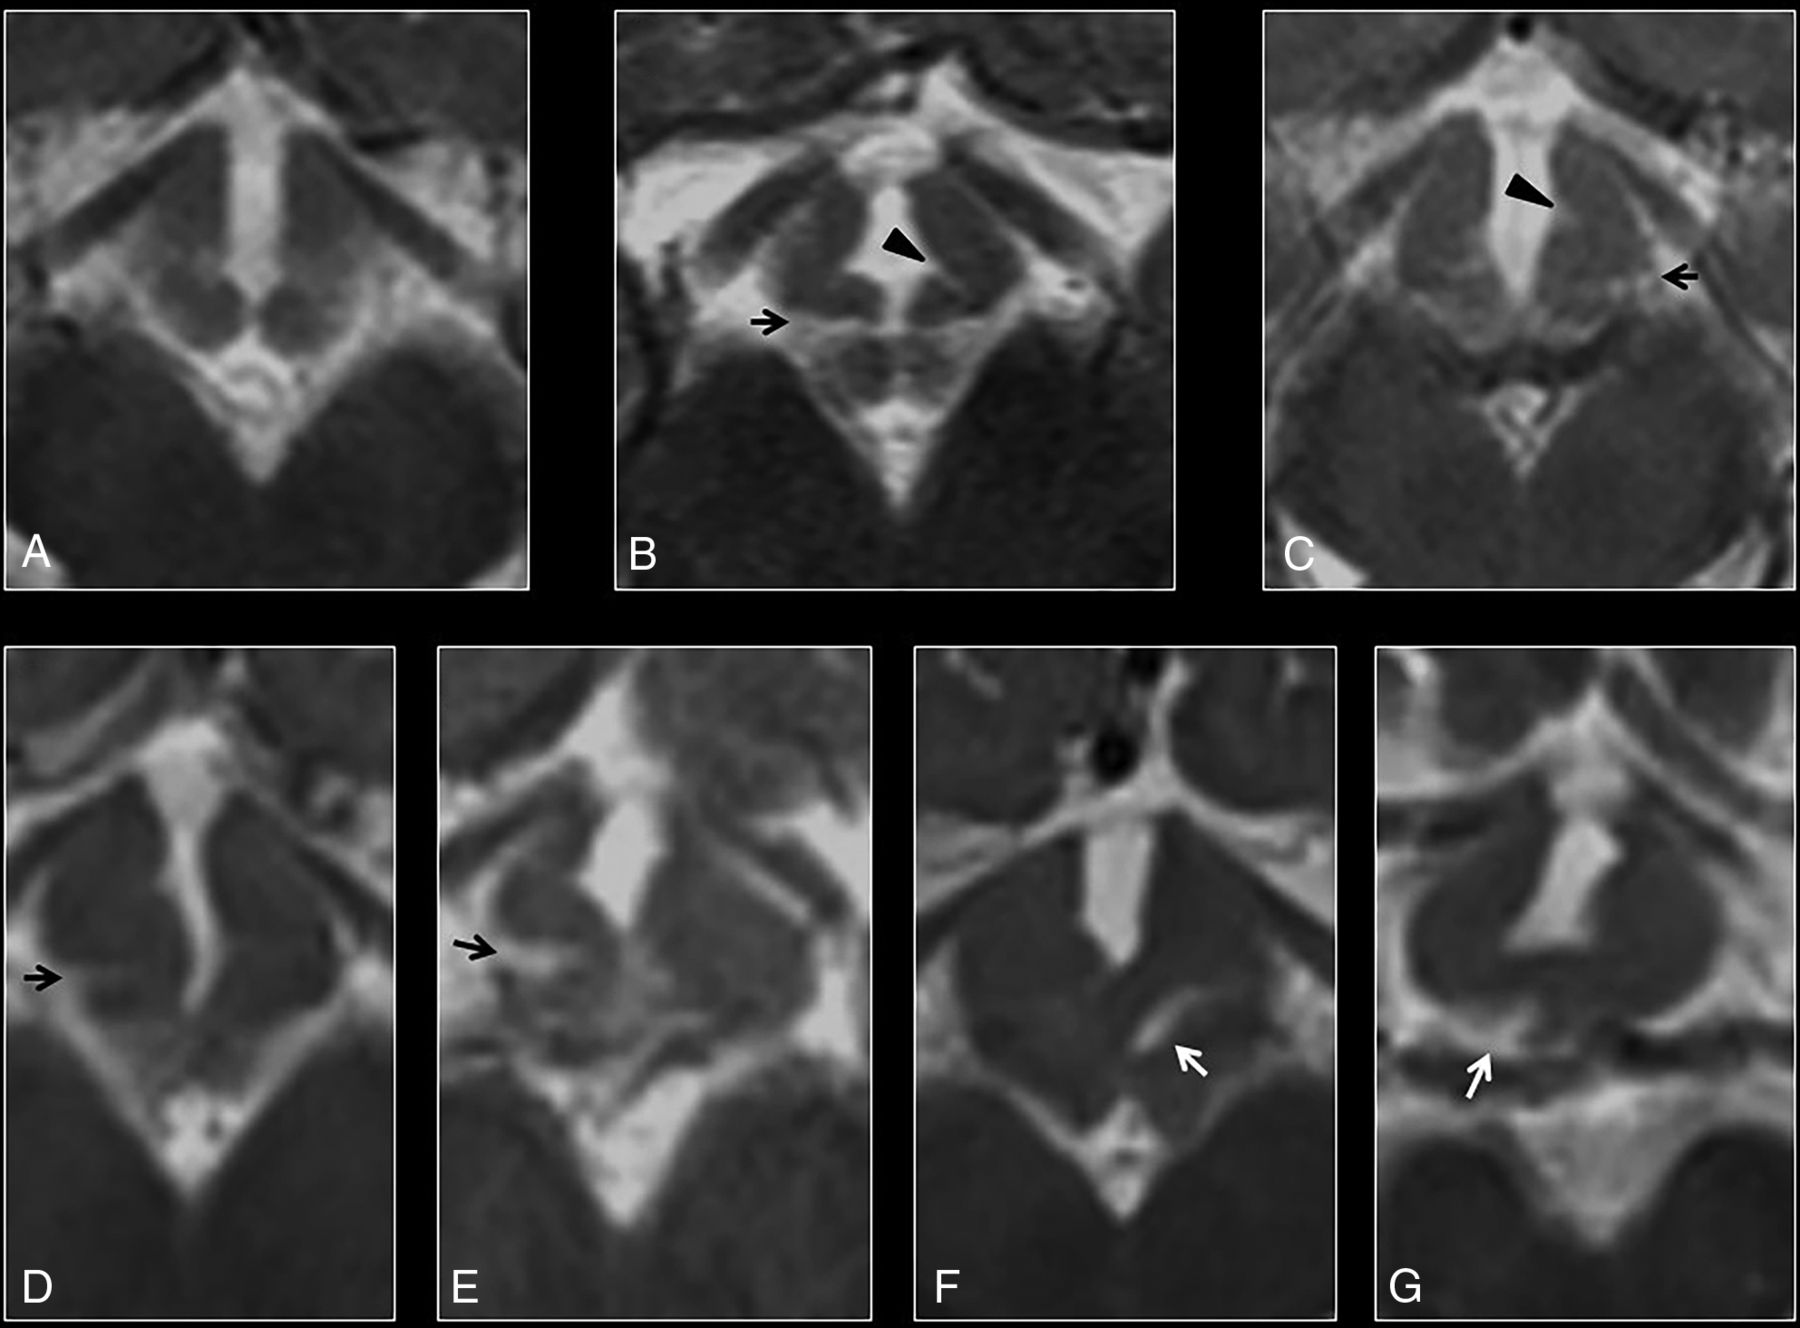

Morphology of the ventromedial hypothalamus was assessed at the level of the optic radiations. While none of the controls showed hypothalamic overfolding (Fig 2A), 7 patients with DFNX2 demonstrated a folded appearance of the ventromedial hypothalamus (P < .001). This hypothalamic overfolding was characterized by an abnormal external or internal cleft in the ventromedial hypothalamus in 7 patients; most (n = 6) showed bilateral abnormal clefts on axial images rather than unilateral ones (Fig 2B–G). All 7 patients showed external clefts compared with internal clefts (pointing toward the third ventricle), which were only present in 5 patients with DFNX2. None of the controls (67 patients) showed hypothalamic clefts (P < .001), and 2 controls had suboptimal axial images. The κ index ranged between 0.76 and 0.95.

A, Axial T2 image of a normal hypothalamus at the level of the optic radiations. B–G, Axial T2 images of the hypothalamus in a patient with DFNX2, which demonstrate progressive folding of the ventromedial hypothalamus. Note the presence of bilateral clefts in most cases, with external clefts being more easily recognizable (arrows). Internal clefts are also noted on B and C (arrowheads).